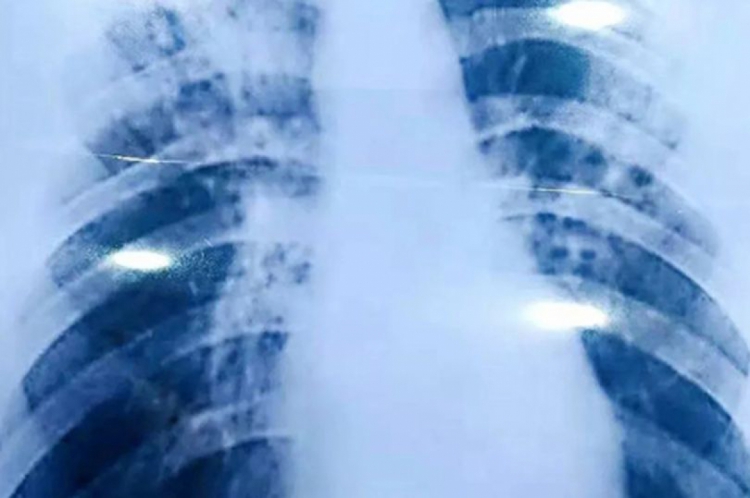

A tuberculose é uma doença infecciosa e transmissível que afeta principalmente os pulmões. Ela é considerada pelo Ministério da Saúde como um “sério problema de saúde pública, com raízes sociais”.